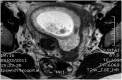

Fig. 3

MRI pelvis at 7 weeks of pregnancy after histological diagnosis.